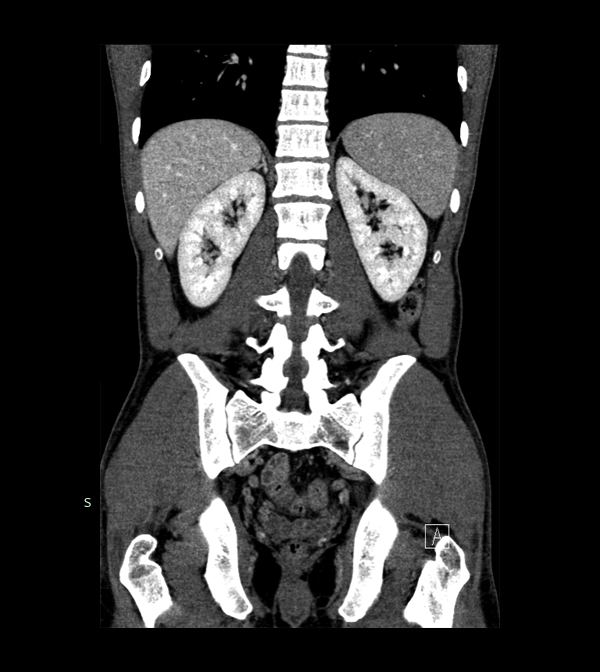

Body

Covers abdominal CT anatomy.